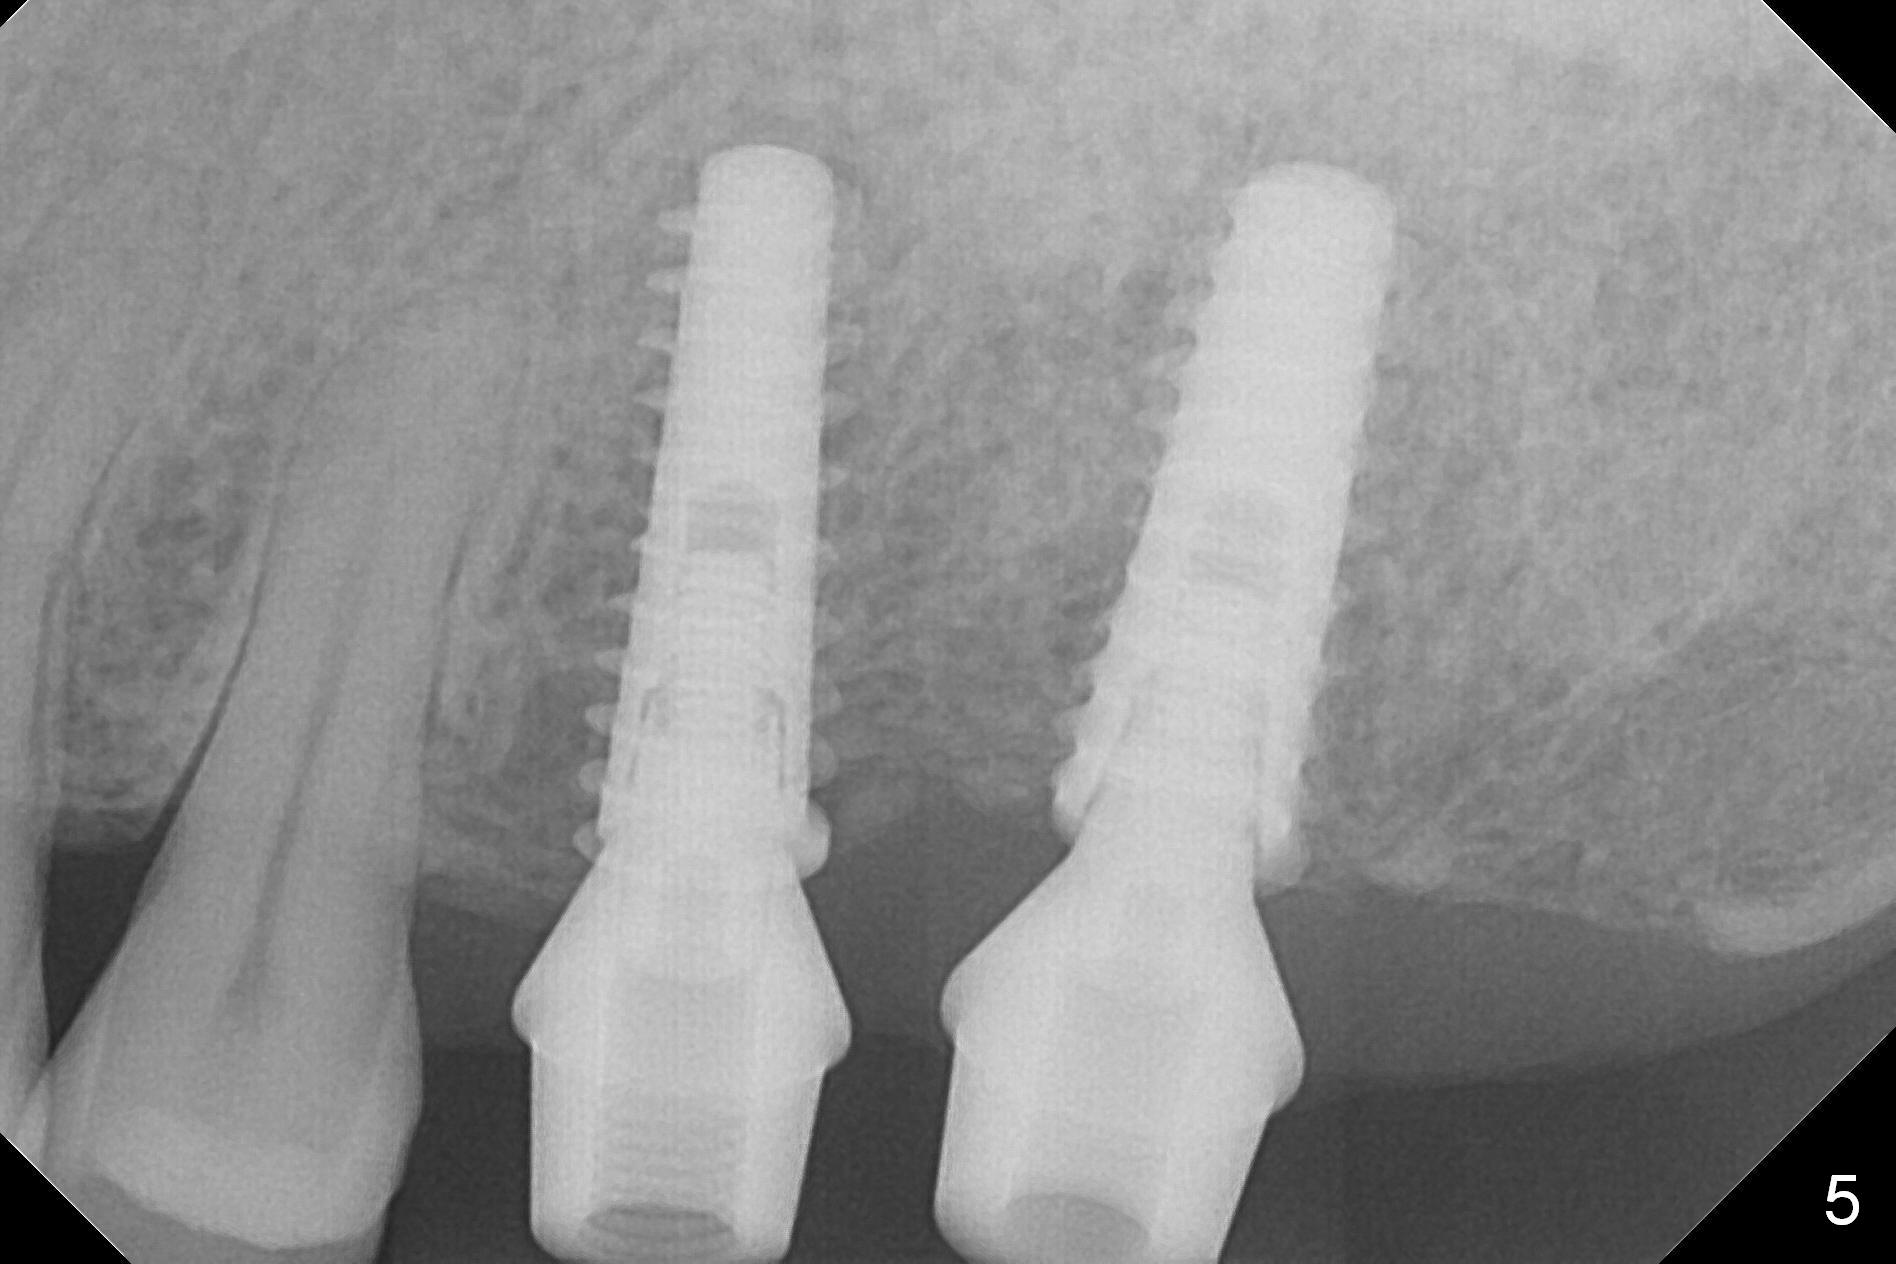

As shown by CT, the ridge at #14 is narrower than that of #15 (confirmed after incision), whereas the density at #14 is higher than that of #15. The osteotomies are established by combination of magic osteotomes and drills after change in trajectory (Fig.1-3). Following placement of 4.5x13 and 5x13 mm IBS implants and 6x4(3) and 6.5x4(3) mm pair abutments at #14 and 15 (Fig.4), flaps are sutured for hemostasis. Since the patient does not tolerate the surgery too well (unstable hypertension and oozing), immediate provisional is delayed. Periodontal dressing is applied instead. While the implants are healing, porcelain chips at the upper anterior bridge. There appears no bone resorption 6 months postop (Fig.5). Impression is taken following changing abutment to 5x4(2) mm at #14 and Diode gingivectomy. A panoramic film is taken 1 year 2 months post cementation. CT taken 2 years post cementation shows relatively good trajectory of these 2 implants (Fig.6,7).